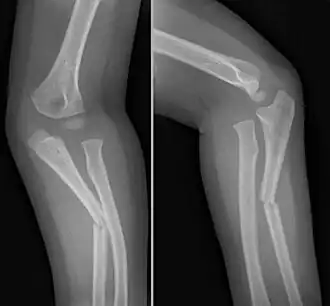

Een monteggiafractuur[1] is een type botbreuk in de onderarm. Er is dan sprake van een breuk van de ellepijp in het proximale deel (het deel wat het dichtst bij de elleboog ligt), samen met een ontwrichting van de kop van het spaakbeen.

Omdat het spaakbeen en de ellepijp stevig met elkaar verbonden zijn door een syndesmose (de membrana interossea antebracchii, een pezige structuur tussen beide botten), zorgt een fractuur van de ellepijp voor een dergelijke kracht op het radio-ulnaire gewricht (het gewricht tussen de ellepijp en het spaakbeen), dat er een ontwrichting ontstaat.

Monteggiafracturen worden meestal operatief behandeld door middel van een open reductie, interne fixatie (ORIF-procedure); de ellepijp wordt weer rechtgezet en met osteosynthesemateriaal (platen, schroeven en/of pennen) gefixeerd. Meestal komt het spaakbeenkopje tijdens de procedure vanzelf weer in de goede stand te staan.